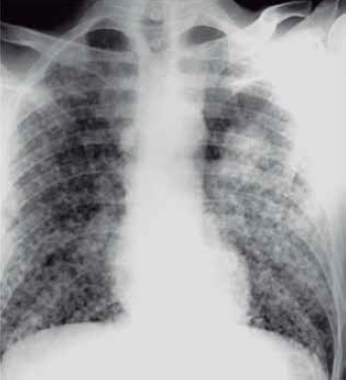

Homem de 59 anos, tabagista de longa data, desempregado e sem exposição ocupacional, é internado com quadro de tosse e dispneia progressiva. Ele não está bem há algum tempo e recebeu vários cursos de antibióticos para “bronquite”. Nos últimos 4 meses não teve acompanhamento médico, e perdeu cerca de 12% do peso corporal. Ao exame físico: queda do estado geral; afebril; roncos e crepitações difusas (tipo velcro). A gasometria arterial mostra PO2 de 68 mmHg com alcalose respiratória compensada leve. O escarro é negativo para tuberculose. A radiografia de tórax é mostrada a seguir.

(Arquivo pessoal; imagem usada com autorização)

Considerando a principal hipótese diagnóstica, constitui um achado que, mais provavelmente, é encontrado